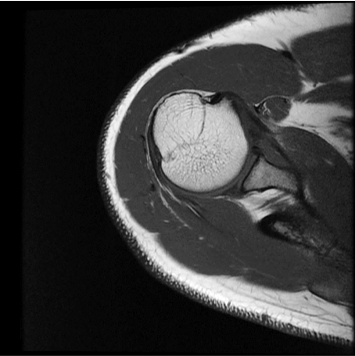

모든 해부학적 부위 적용가능

IAI는 AI Deep learning을 통해 기존 장비의 촬영 프로토콜을 최적화합니다.

기존 프로토콜 대비 촬영 시간을 50% 단축시키며, 이미지 퀄리티는 증가합니다.